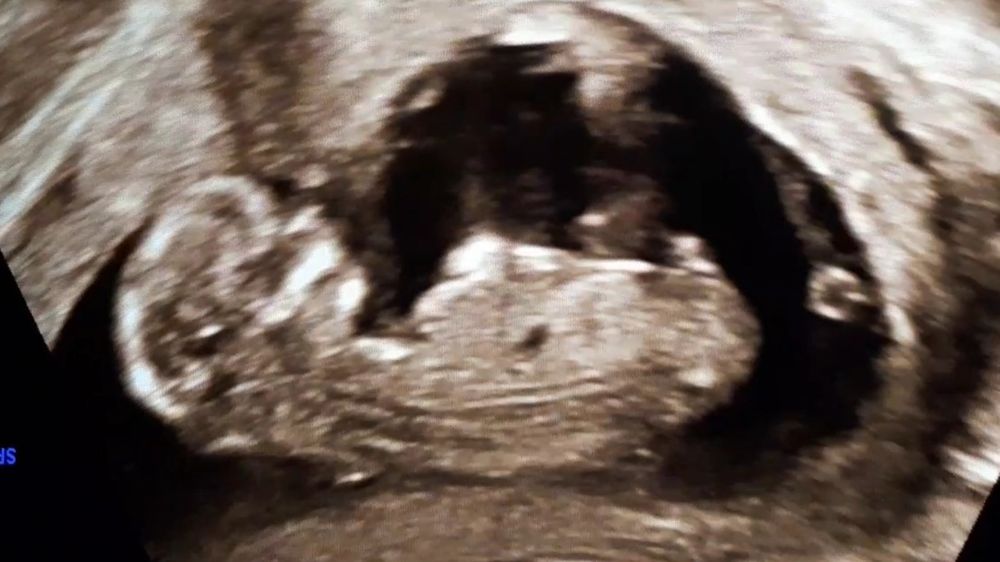

Сегодня сходила на первый скрининг, по узи, сказали, всё хорошо. По м срок 12+3, по ктр 12+6, ТВП 1,55, БПД 20, нк визуализируется 1,9

Врач предположила мальчика, но сказала, что лучше ещё перепроверить попозже.

В начале узи малыш спал, я даже испугалась, почему такой спокойный, но потом как заактивничал, что она его еле ловила, чтобы всё основательно проверить)) но посмотрели всё со всех сторон, даже увидели, как сжимает и разжимает свои крохотные пальчики😍